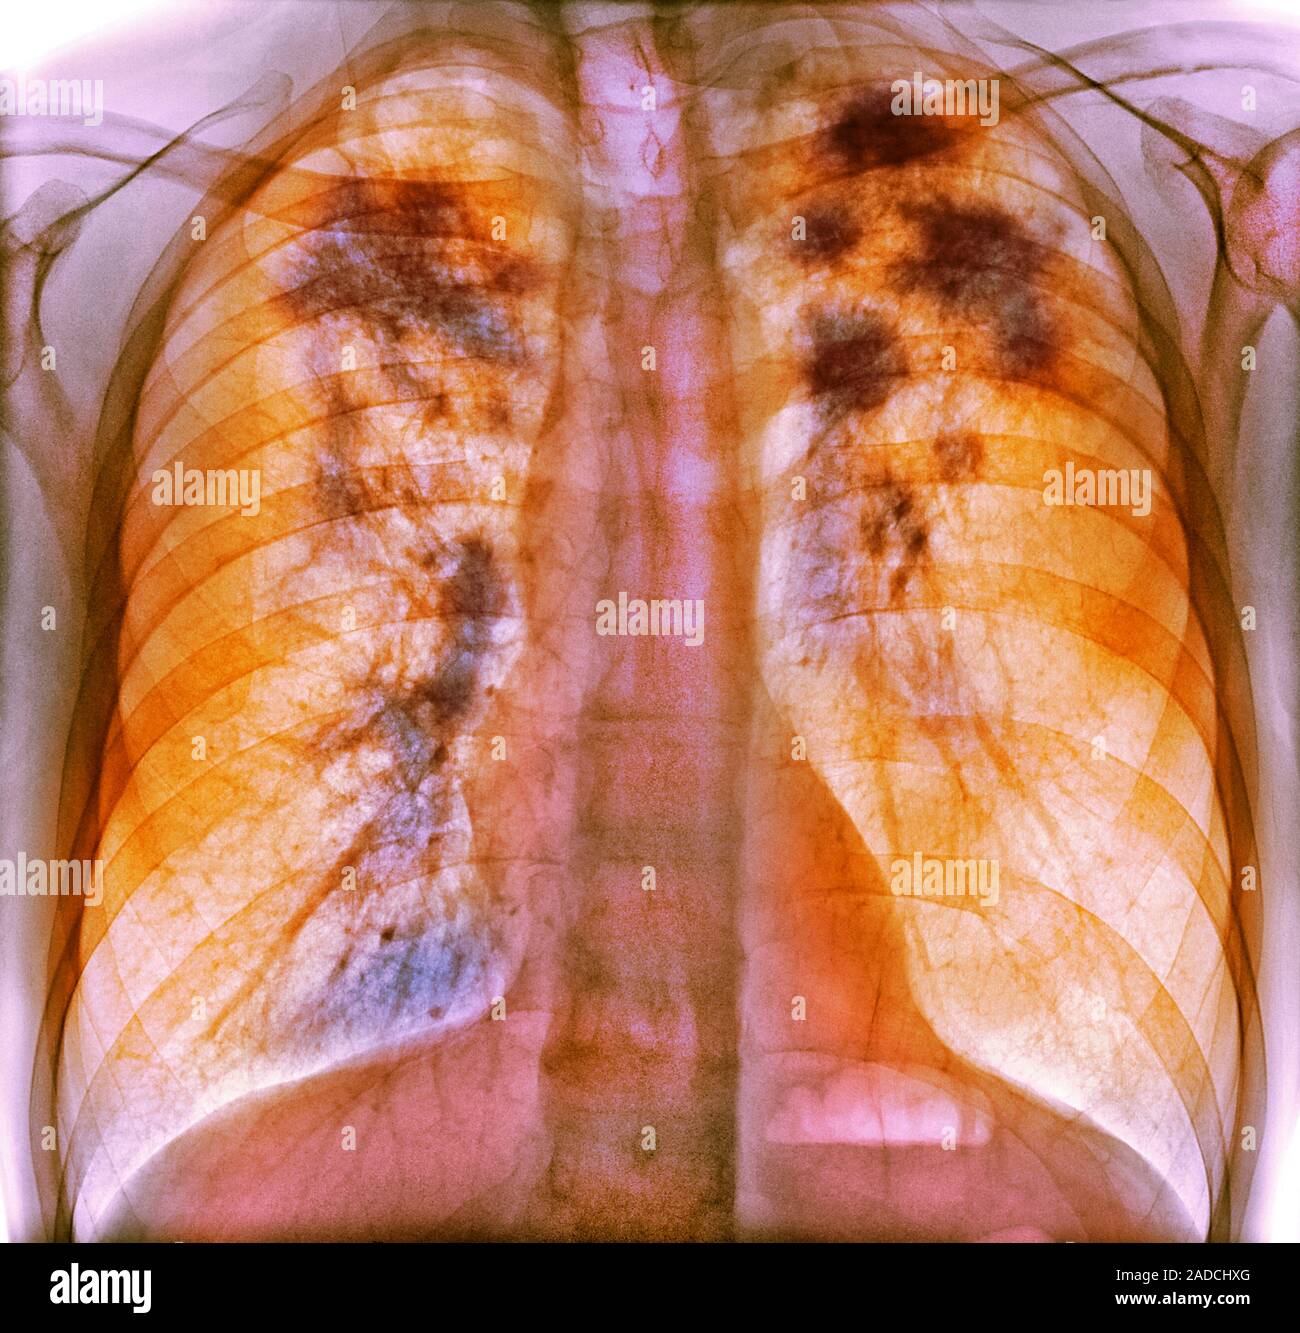

From www.researchgate.net

Chest radiography shows multiple nodules and masses involving both What Does Patch On Lung Mean A spot on the lungs usually refers to a pulmonary nodule. A lung (pulmonary) nodule is an abnormal growth that forms in a lung. You may have one nodule on the lung or several nodules. A lung nodule is a small growth in the lung that can show up on a ct scan. Because they rarely have symptoms, they are.. What Does Patch On Lung Mean.